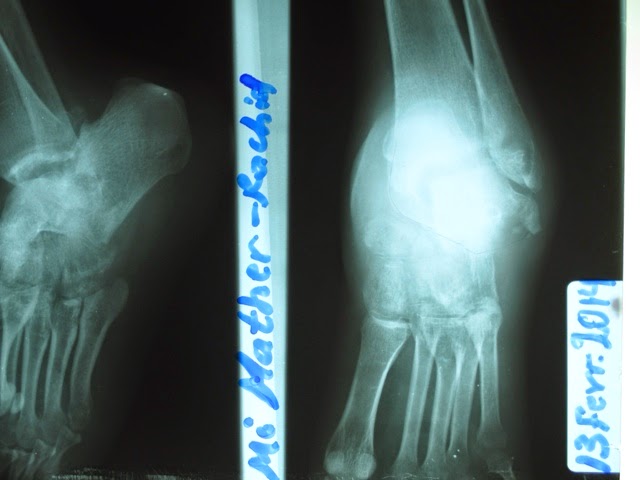

This young lady, in her mid 20's, sustained this ankle fracture in a motorcycle accident. (Which is where most of our Ortho cases come from.) She presented several months after the accident. This was beyond our ability to treat, as ankle/foot fracture of this nature are a challenge even to orthopods and podiatrists. When we told her we wouldn't operate, she fell to the ground, crying and pleading that we would do something for her. Then we called in her mother to console her, and when we informed her the same news we told her daughter, she also fell to the floor and did the same. They weren't without hope, as there is a doctor in a nearby town who was willing to operate, but they were hoping they would have something done at Nyankunde.